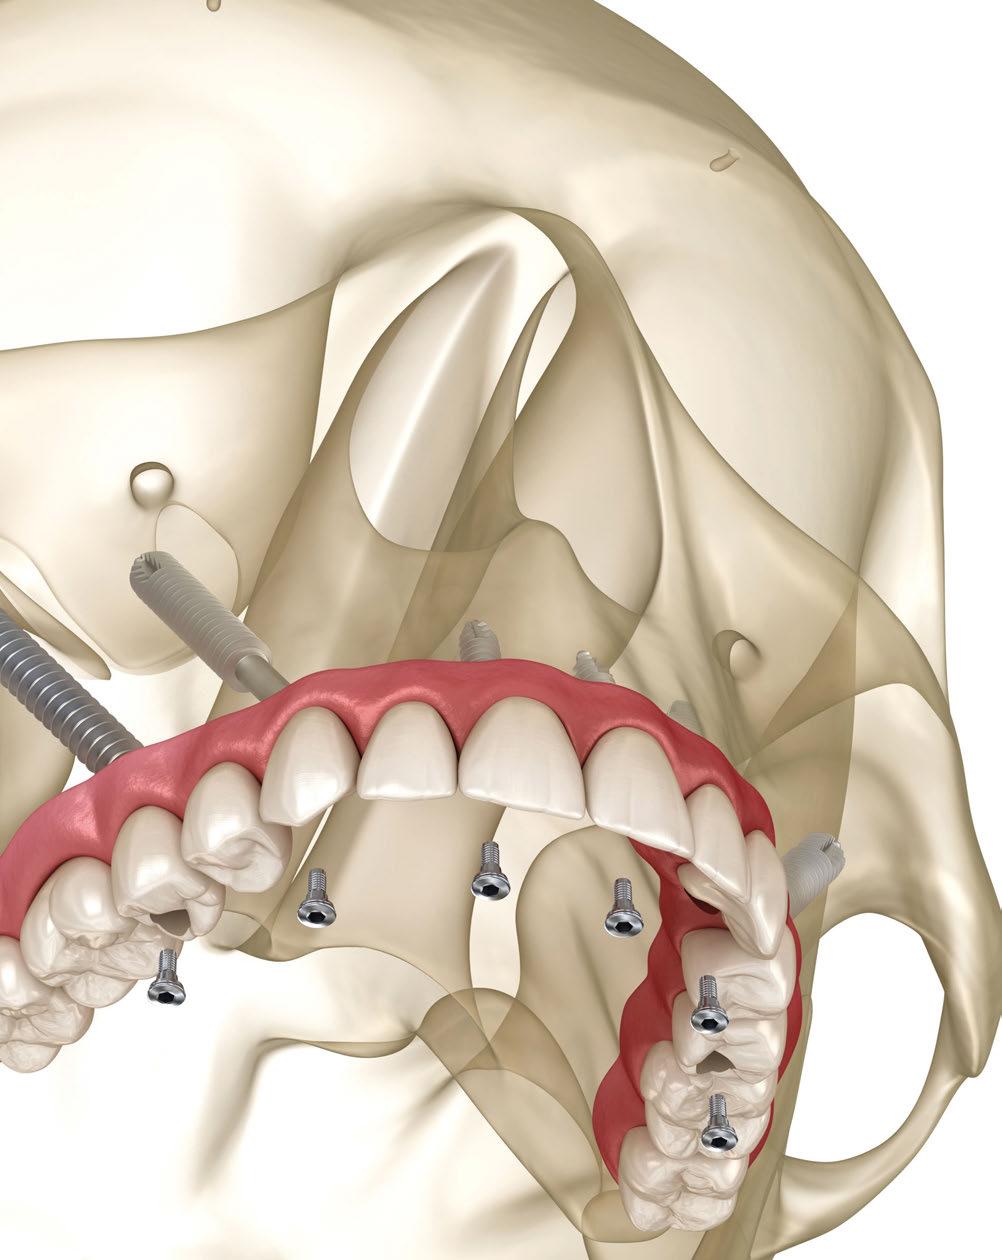

Una puesta al día en implantes cigomáticos

Es evidente que los implantes cigomáticos se han convertido en la opción más eficaz en el tratamiento de los pacientes con atrofia severa del maxilar superior. Puesto que esta técnica evita la necesidad de realizar injertos óseos, el tiempo de tratamiento se reduce de forma drástica, al igual que las molestias para el paciente. La depuración de la técnica quirúrgica, la incorporación de nuevas tecnologías, sobre todo la cirugía por navegación, así como el diseño de prometedores nuevos sistemas de implantes cigomáticos, nos ofrecen unos resultados excelentes, predecibles y sin apenas complicaciones. Por el contrario, su mayor hándicap es la curva de aprendizaje de esta técnica, la cual se restringe, hoy por hoy, a profesionales que cuentan previamente con destreza y experiencia quirúrgica notables.

El campo de los implantes cigomáticos ha evolucionado mucho desde la técnica quirúrgica original descrita por el Prof. Brånemark en la década de los ochenta. Aquella técnica supuso un gran paso en la rehabilitación del maxilar atrófico, pero era controvertida porque el recorrido intrasinusal del implante podía originar complicaciones sinusales y, en algunas ocasiones, emergencias demasiado palatinizadas. Sin embargo, ya los

primeros resultados de estudios clínicos mostraron tasas de supervivencia cercanas al 100%. Con el tiempo y la investigación clínica, estos problemas iniciales se han ido superando gracias a las innovaciones constantes, a las técnicas extrasinusales, a las técnicas «Guiadas por la Anatomía» y al diseño de nuevos sistemas de implantes cigomáticos. Las mejoras en los softwares de planificación quirúrgica también han contribuido a la depuración de la técnica. Todo ello ha hecho que los implantes

cigomáticos sean un tratamiento cada vez más maduro, seguro y predecible para los pacientes.